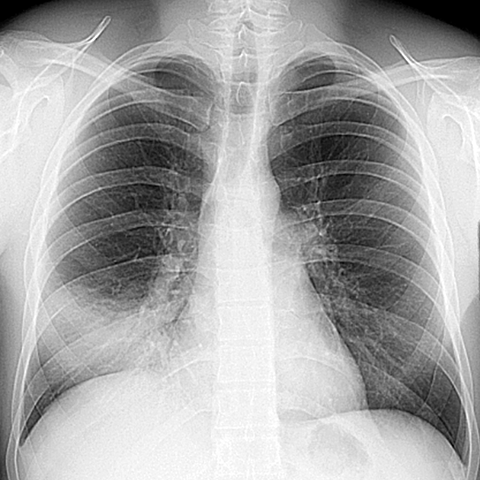

Silhouette Sign, RML Pneumonia (PA CXR) [1 of 4]